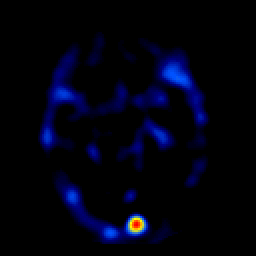

overlay -- Slice #12

[Home][Help][Clinical] Slice 12